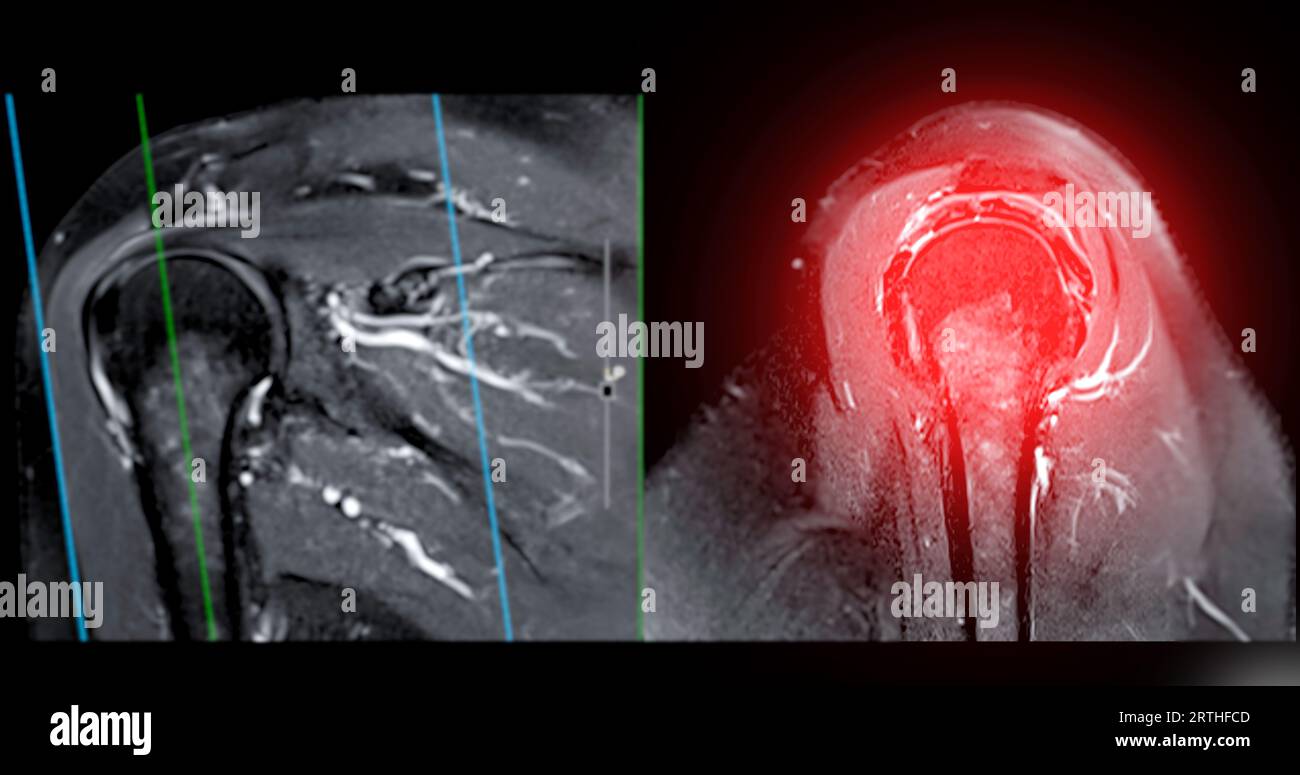

Resonance Imaging or MRI of Shoulder Joint Coronal T2 FS and PDW for diagnostic What Can Mri Of Shoulder Detect magnetic resonance imaging (mri) of the shoulder is done to: magnetic resonance imaging (mri) of the shoulder uses a powerful magnetic field, radio waves and a computer to produce. The mri allows accurate assessment of. a shoulder mri is a test that uses a magnetic field to take pictures of your shoulder. A shoulder mri can diagnose. What Can Mri Of Shoulder Detect.

Resonance Imaging or MRI of Shoulder Joint for diagnostic shoulder pain Stock Photo Alamy What Can Mri Of Shoulder Detect A shoulder mri can diagnose tears of the rotator cuff, labrum, and tendons. a shoulder mri is a test that uses a magnetic field to take pictures of your shoulder. magnetic resonance imaging, or mri, uses a magnet to examine the inside of your body, useful for diagnosing shoulder pain and. the evaluation of the shoulder, and. What Can Mri Of Shoulder Detect.